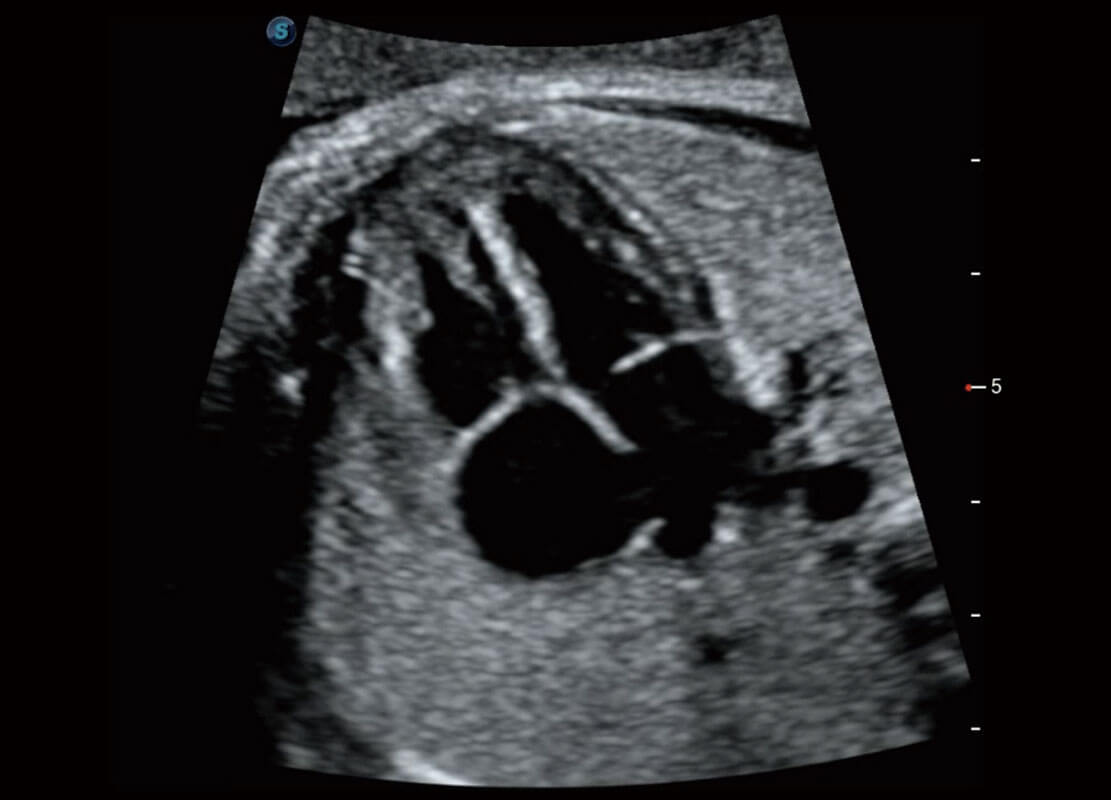

P60搭载一系列胎儿心脏成像技术,实现精细的胎儿心脏评估。

四腔切面

胎心容积成像